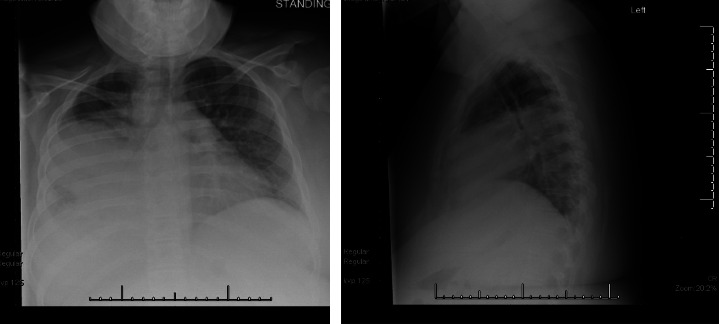

芽生菌病是一种罕见的真菌感染,由吸入皮炎芽生菌孢子引起。这种真菌感染几乎可以影响每个器官系统,尽管肺部疾病是最常见的。肺芽孢菌病的表现变化很大,从临床无症状到需要重症监护的严重呼吸衰竭。本病例系列描述了两个兄弟姐妹的临床表现、诊断挑战、管理和结果,他们患有严重的肺芽孢菌病,并发展为儿童急性呼吸窘迫综合征,需要机械通气和静脉-静脉体外膜氧合(VV-ECMO)。尽管相对罕见,但在呼吸道症状对经验性抗菌治疗无反应的患者中,应考虑芽生菌病,特别是在流行地区。早期诊断和及时开始适当的抗真菌治疗对良好的结果至关重要。此外,对于严重的肺芽孢菌病,早期开始ECMO可能有利于延缓时间,以便有足够的时间对抗真菌治疗产生充分的反应。

Blastomycosis is a rare fungal infection caused by the inhalation of Blastomyces dermatitidis spores. Infection with this fungus can impact nearly every organ system, though pulmonary disease is the most common. Presentations of pulmonary blastomycosis are highly variable, ranging from clinically asymptomatic to severe respiratory failure requiring intensive care. This case series describes the clinical presentation, diagnostic challenges, management, and outcomes of two siblings with severe pulmonary blastomycosis that progressed to pediatric acute respiratory distress syndrome requiring mechanical ventilation and venovenous extracorporeal membrane oxygenation (VV-ECMO). Despite being relatively uncommon, blastomycosis should be considered in patients with respiratory symptoms not responding to empiric antibacterial therapy, particularly in endemic regions. Early diagnosis and prompt initiation of appropriate antifungal therapy are crucial for favorable outcomes. Additionally, early initiation of ECMO for severe pulmonary blastomycosis may be beneficial in temporizing to allow time for sufficient response to antifungal therapy.